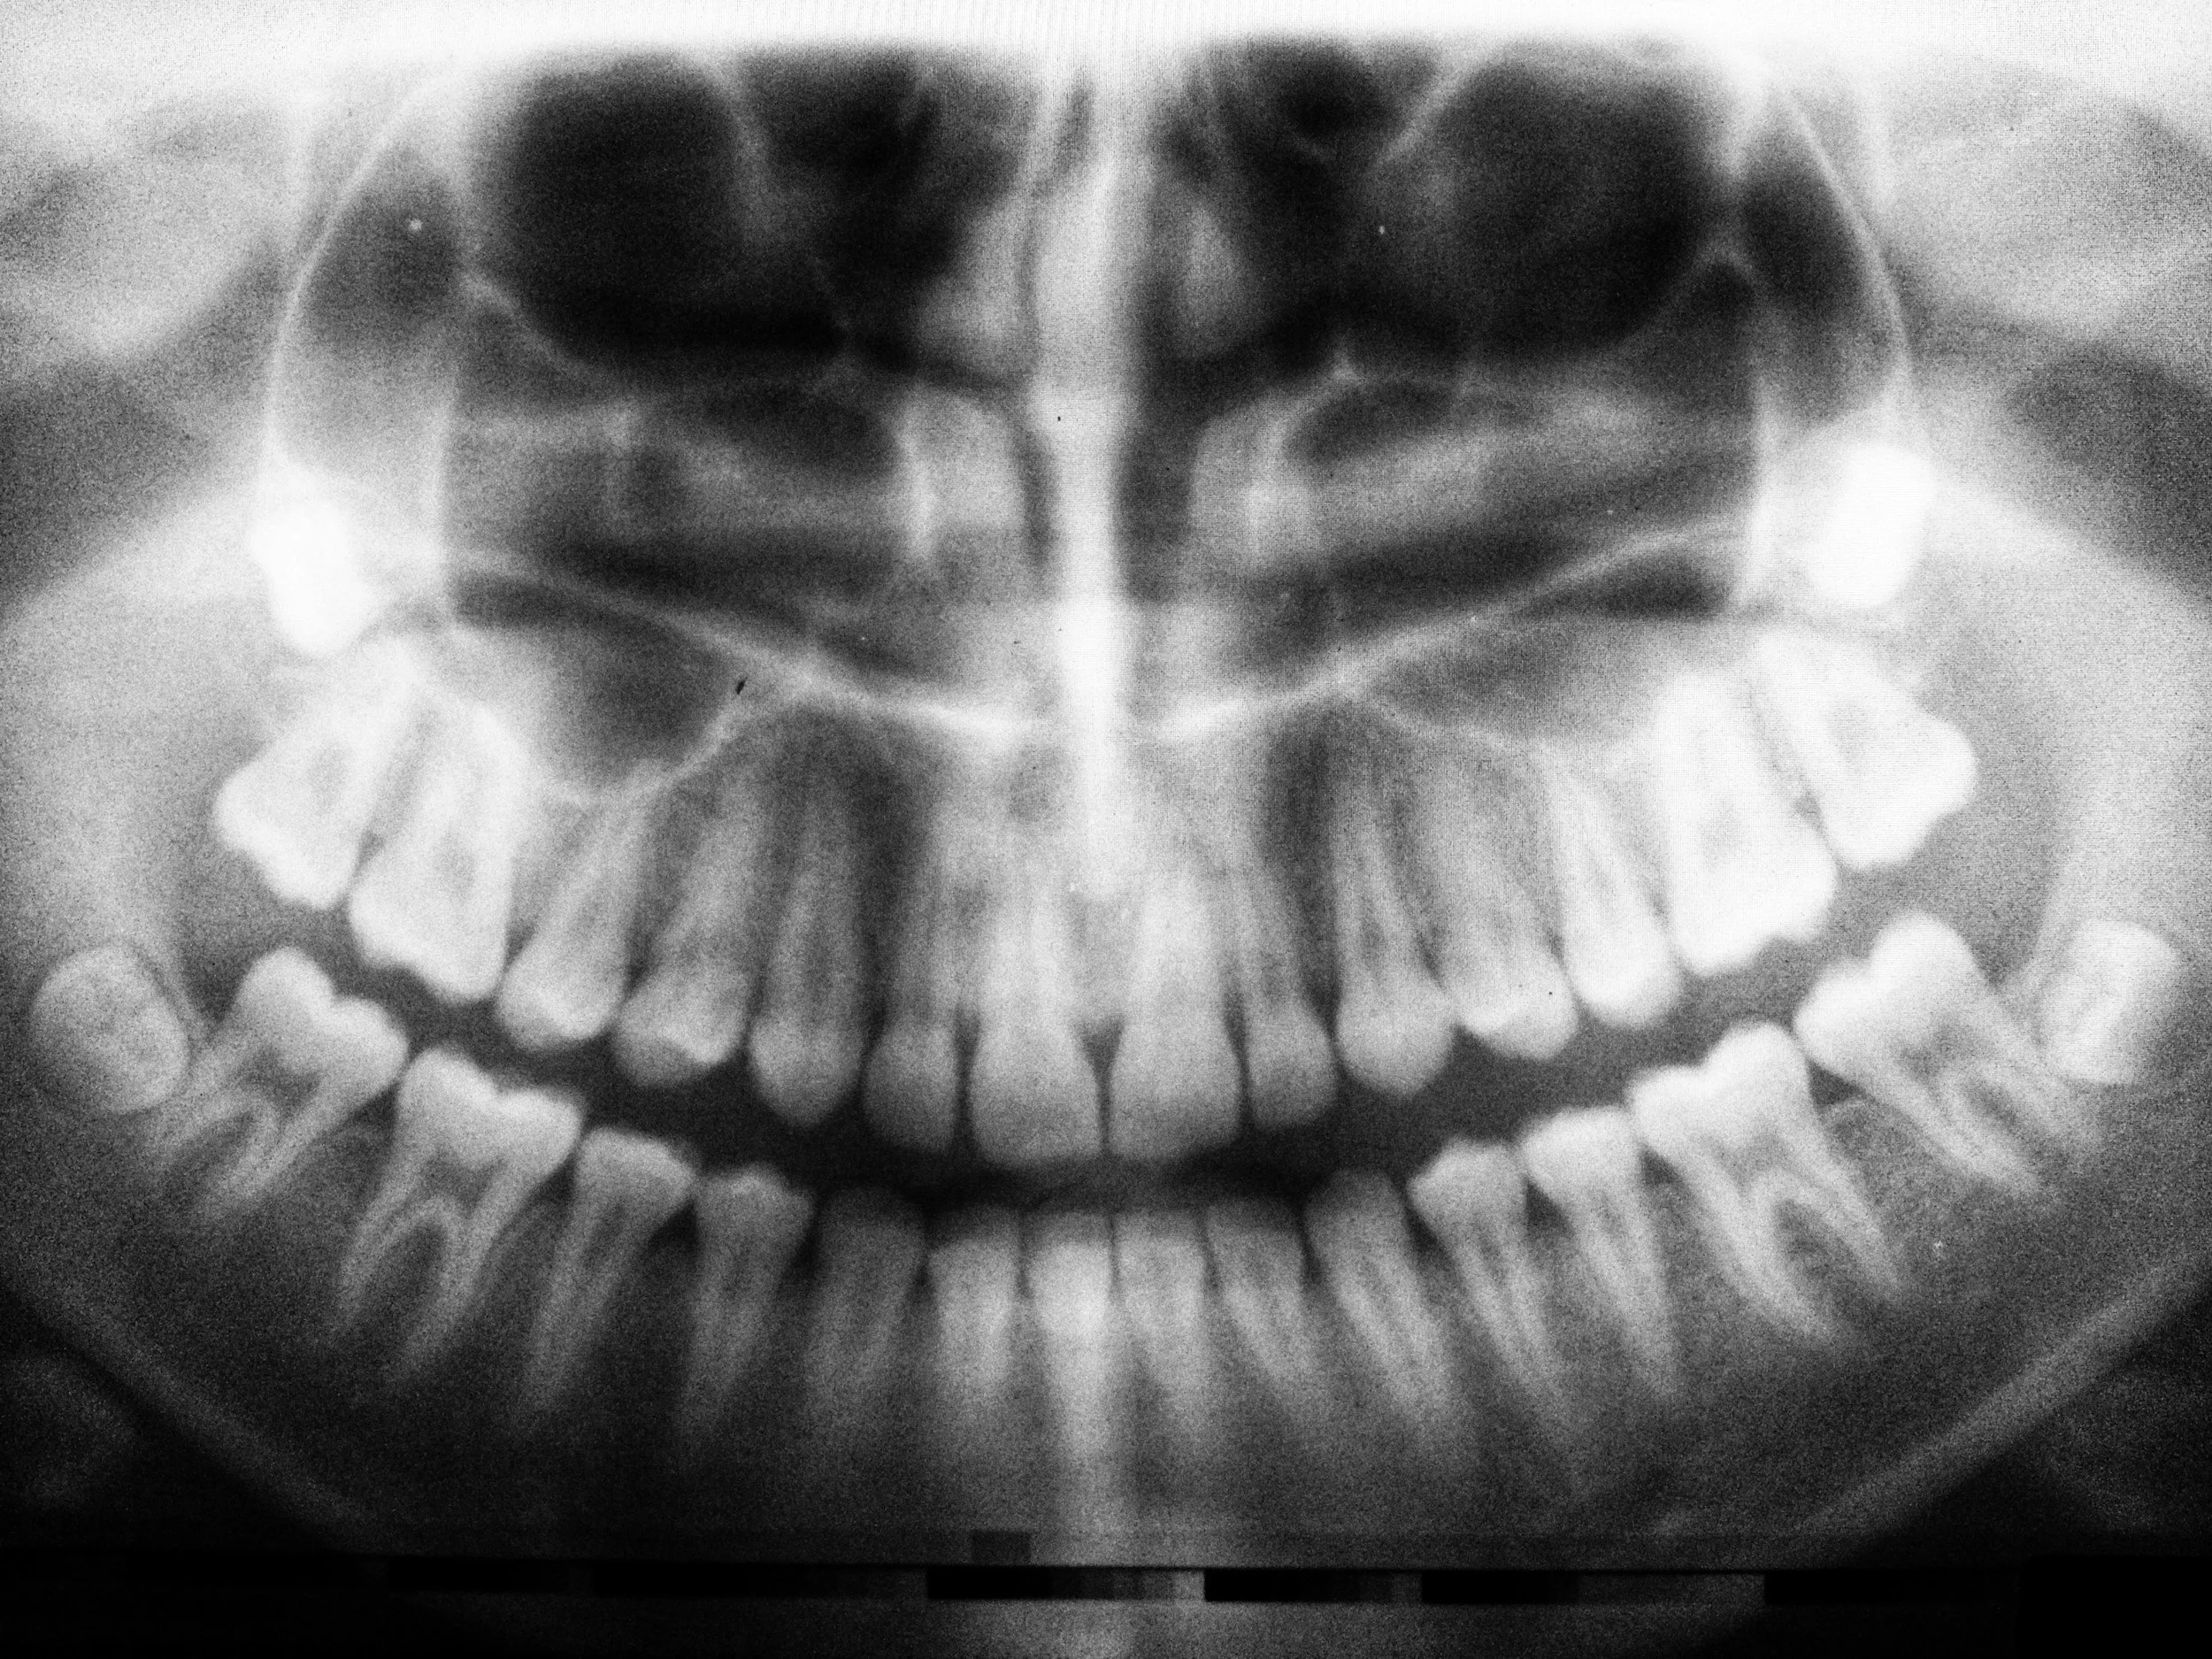

panoramic xray